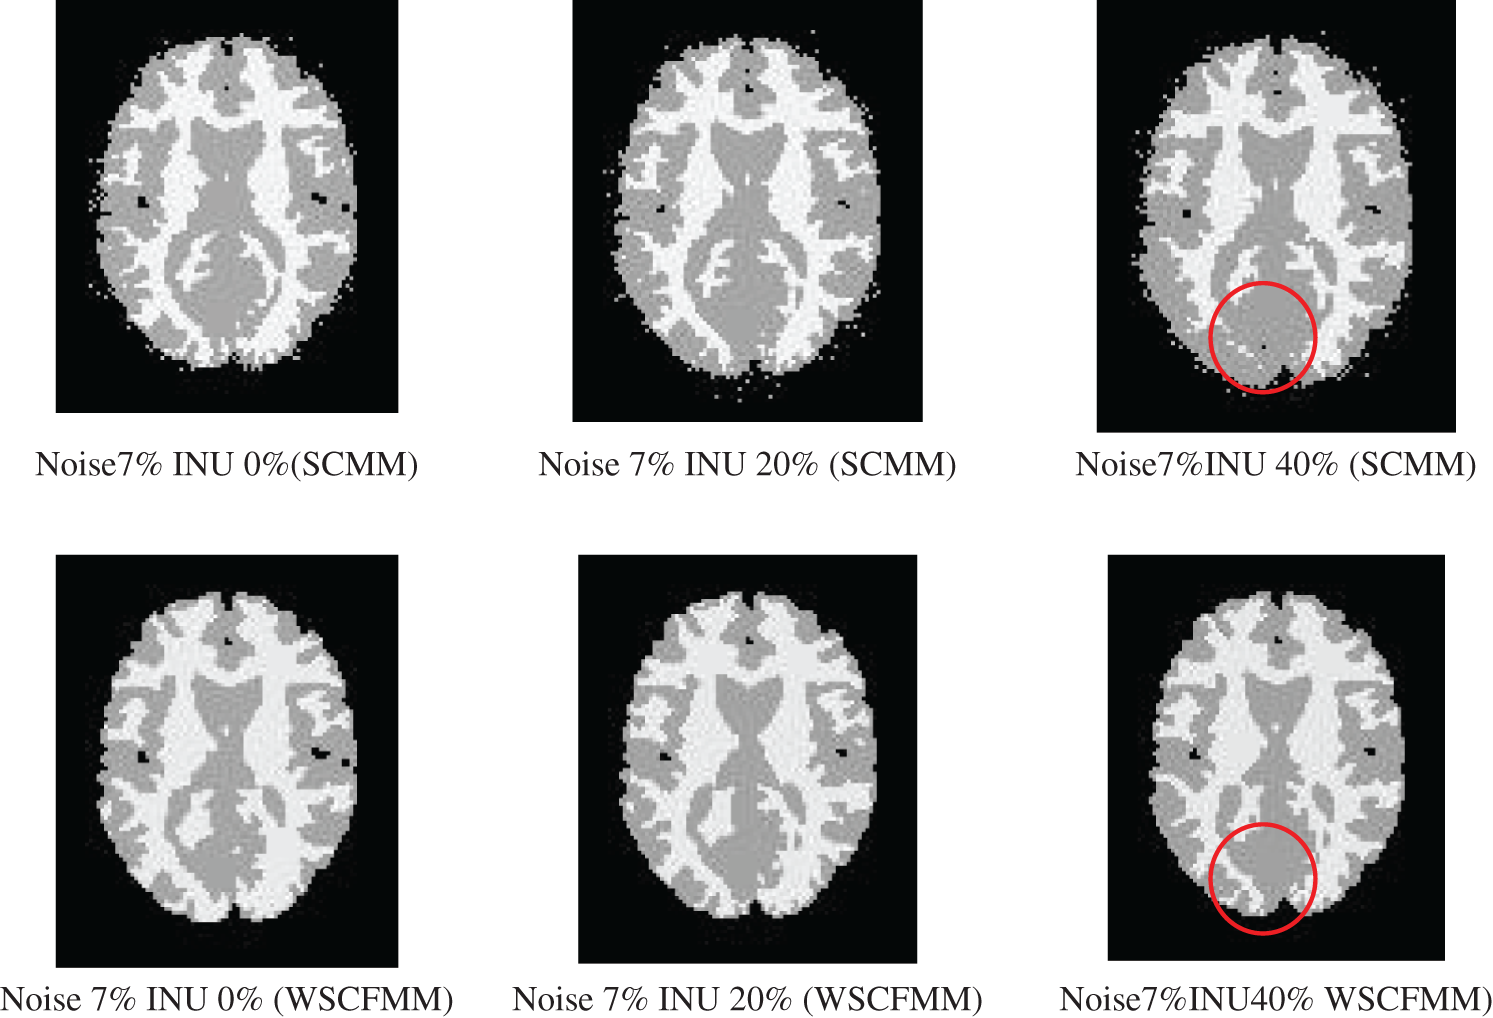

The visual comparison between the results produced by both the models showed that WSCFMM was able to control the outliers and gave an appreciative level of performance in ideal conditions and in conditions where the candidate image is affected from intensity INU and/or noise.

Figs. 3 and 4 show the performance of WSCMM in comparison to SCMM. The results shown in the figures were obtained from the images affected with a higher level of noise, i.e., 7% and 9%, combined with different levels of INU. The visual investigations of these results show that besides outliers, SCMM is also unable to provide a well-defined segment. The circled region in Figs. 3 and 4 provides important observations which led us to the conclusion that a substantial portion of the information is missing. However, at the same settings of noise and INU, WSCFMM not only controlled the outliers but it also captured that missing information.

Figure 3: Visual comparison of images with 7% noise and INU varying from 0% to 40% segmented by SCMM and WSCFMM